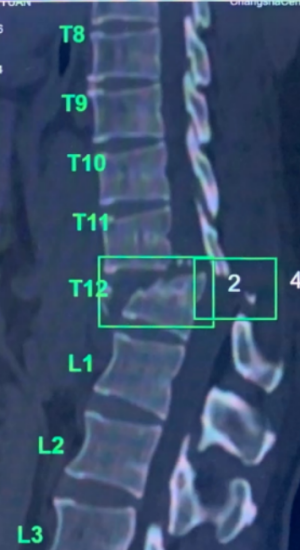

急诊科,CT和磁共振检查提示胸腰段T11、T12椎体爆裂性骨折并脱位,并脊髓损伤伴截瘫,这是脊柱脊髓损伤中最严重的情况。

术前检查示胸腰段T11、T12椎体爆裂性骨折并脱位